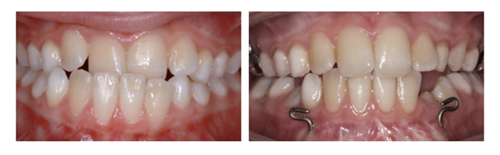

Dit barn er henvist til Tand, Mund,- og Kæbekirurgisk afdeling for indsættelse af knogleforankring (mentoplate og ganeskruer) grundet en kæbeafvigelse (underbid). Operationen er første del af dit barns behandlingsforløb, som efterfølgende vil omfatte 12-18 måneder med elastiktræk mellem bøjlen i overkæben og krogene i underkæben (se fotos). Elastikkerne vil stimulere væksten af overkæben, så underbiddet gradvist bliver mindre for til sidst at forsvinde helt (se fotos).

Operationen foregår i fuld bedøvelse og efterfølgende kontroller og behandling foretages i kommunalt regi. I forbindelse med operationen indsættes 2 ganeskruer samt en lille metalskinne med kroge på underkæben, (se fotos). Det bliver syet i undermunden med tråde som er selvopløsende.

Sammenbid set fra siden før og efter behandling med elastiktræk.